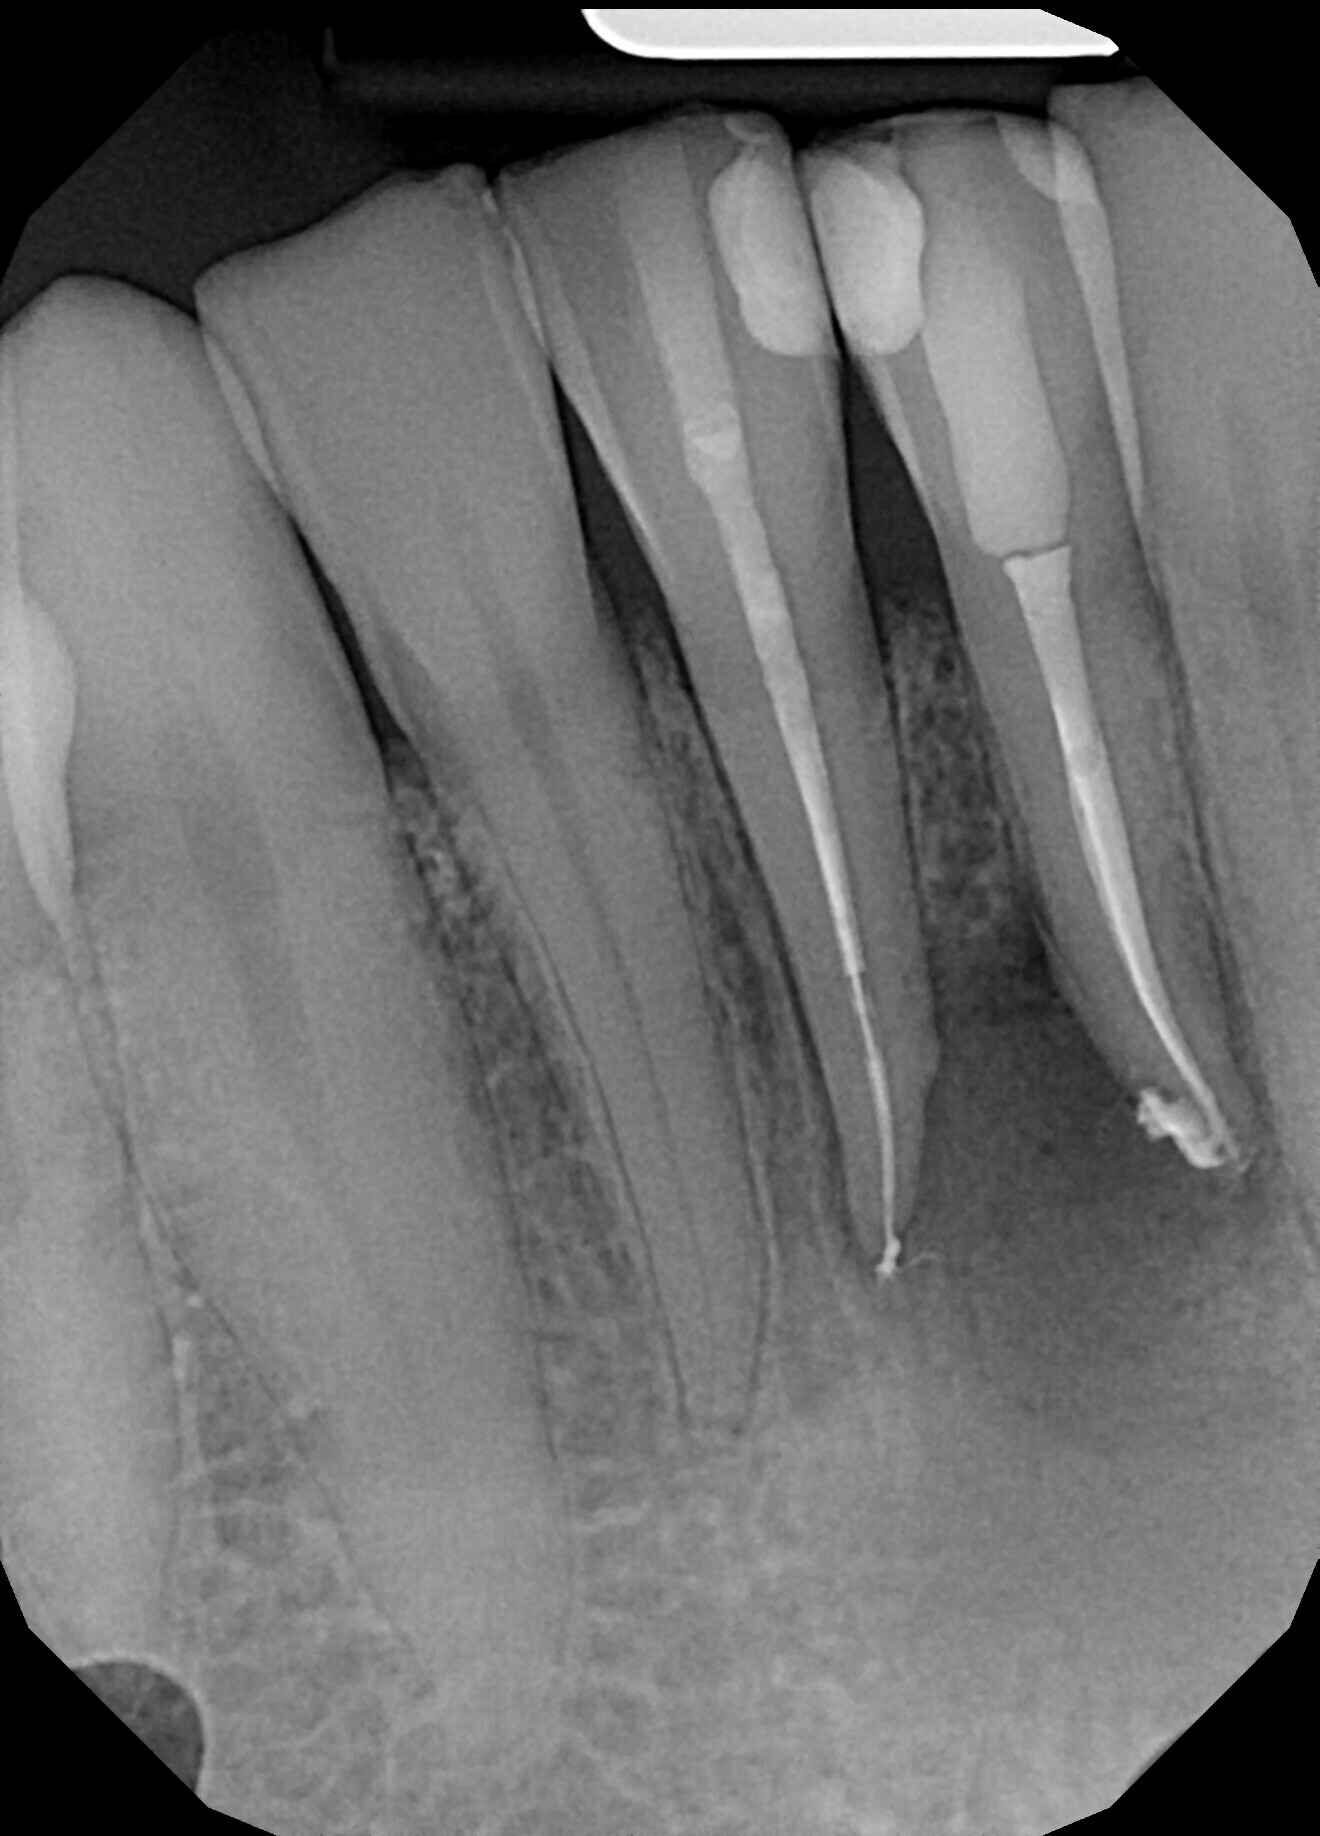

Fig. 8.